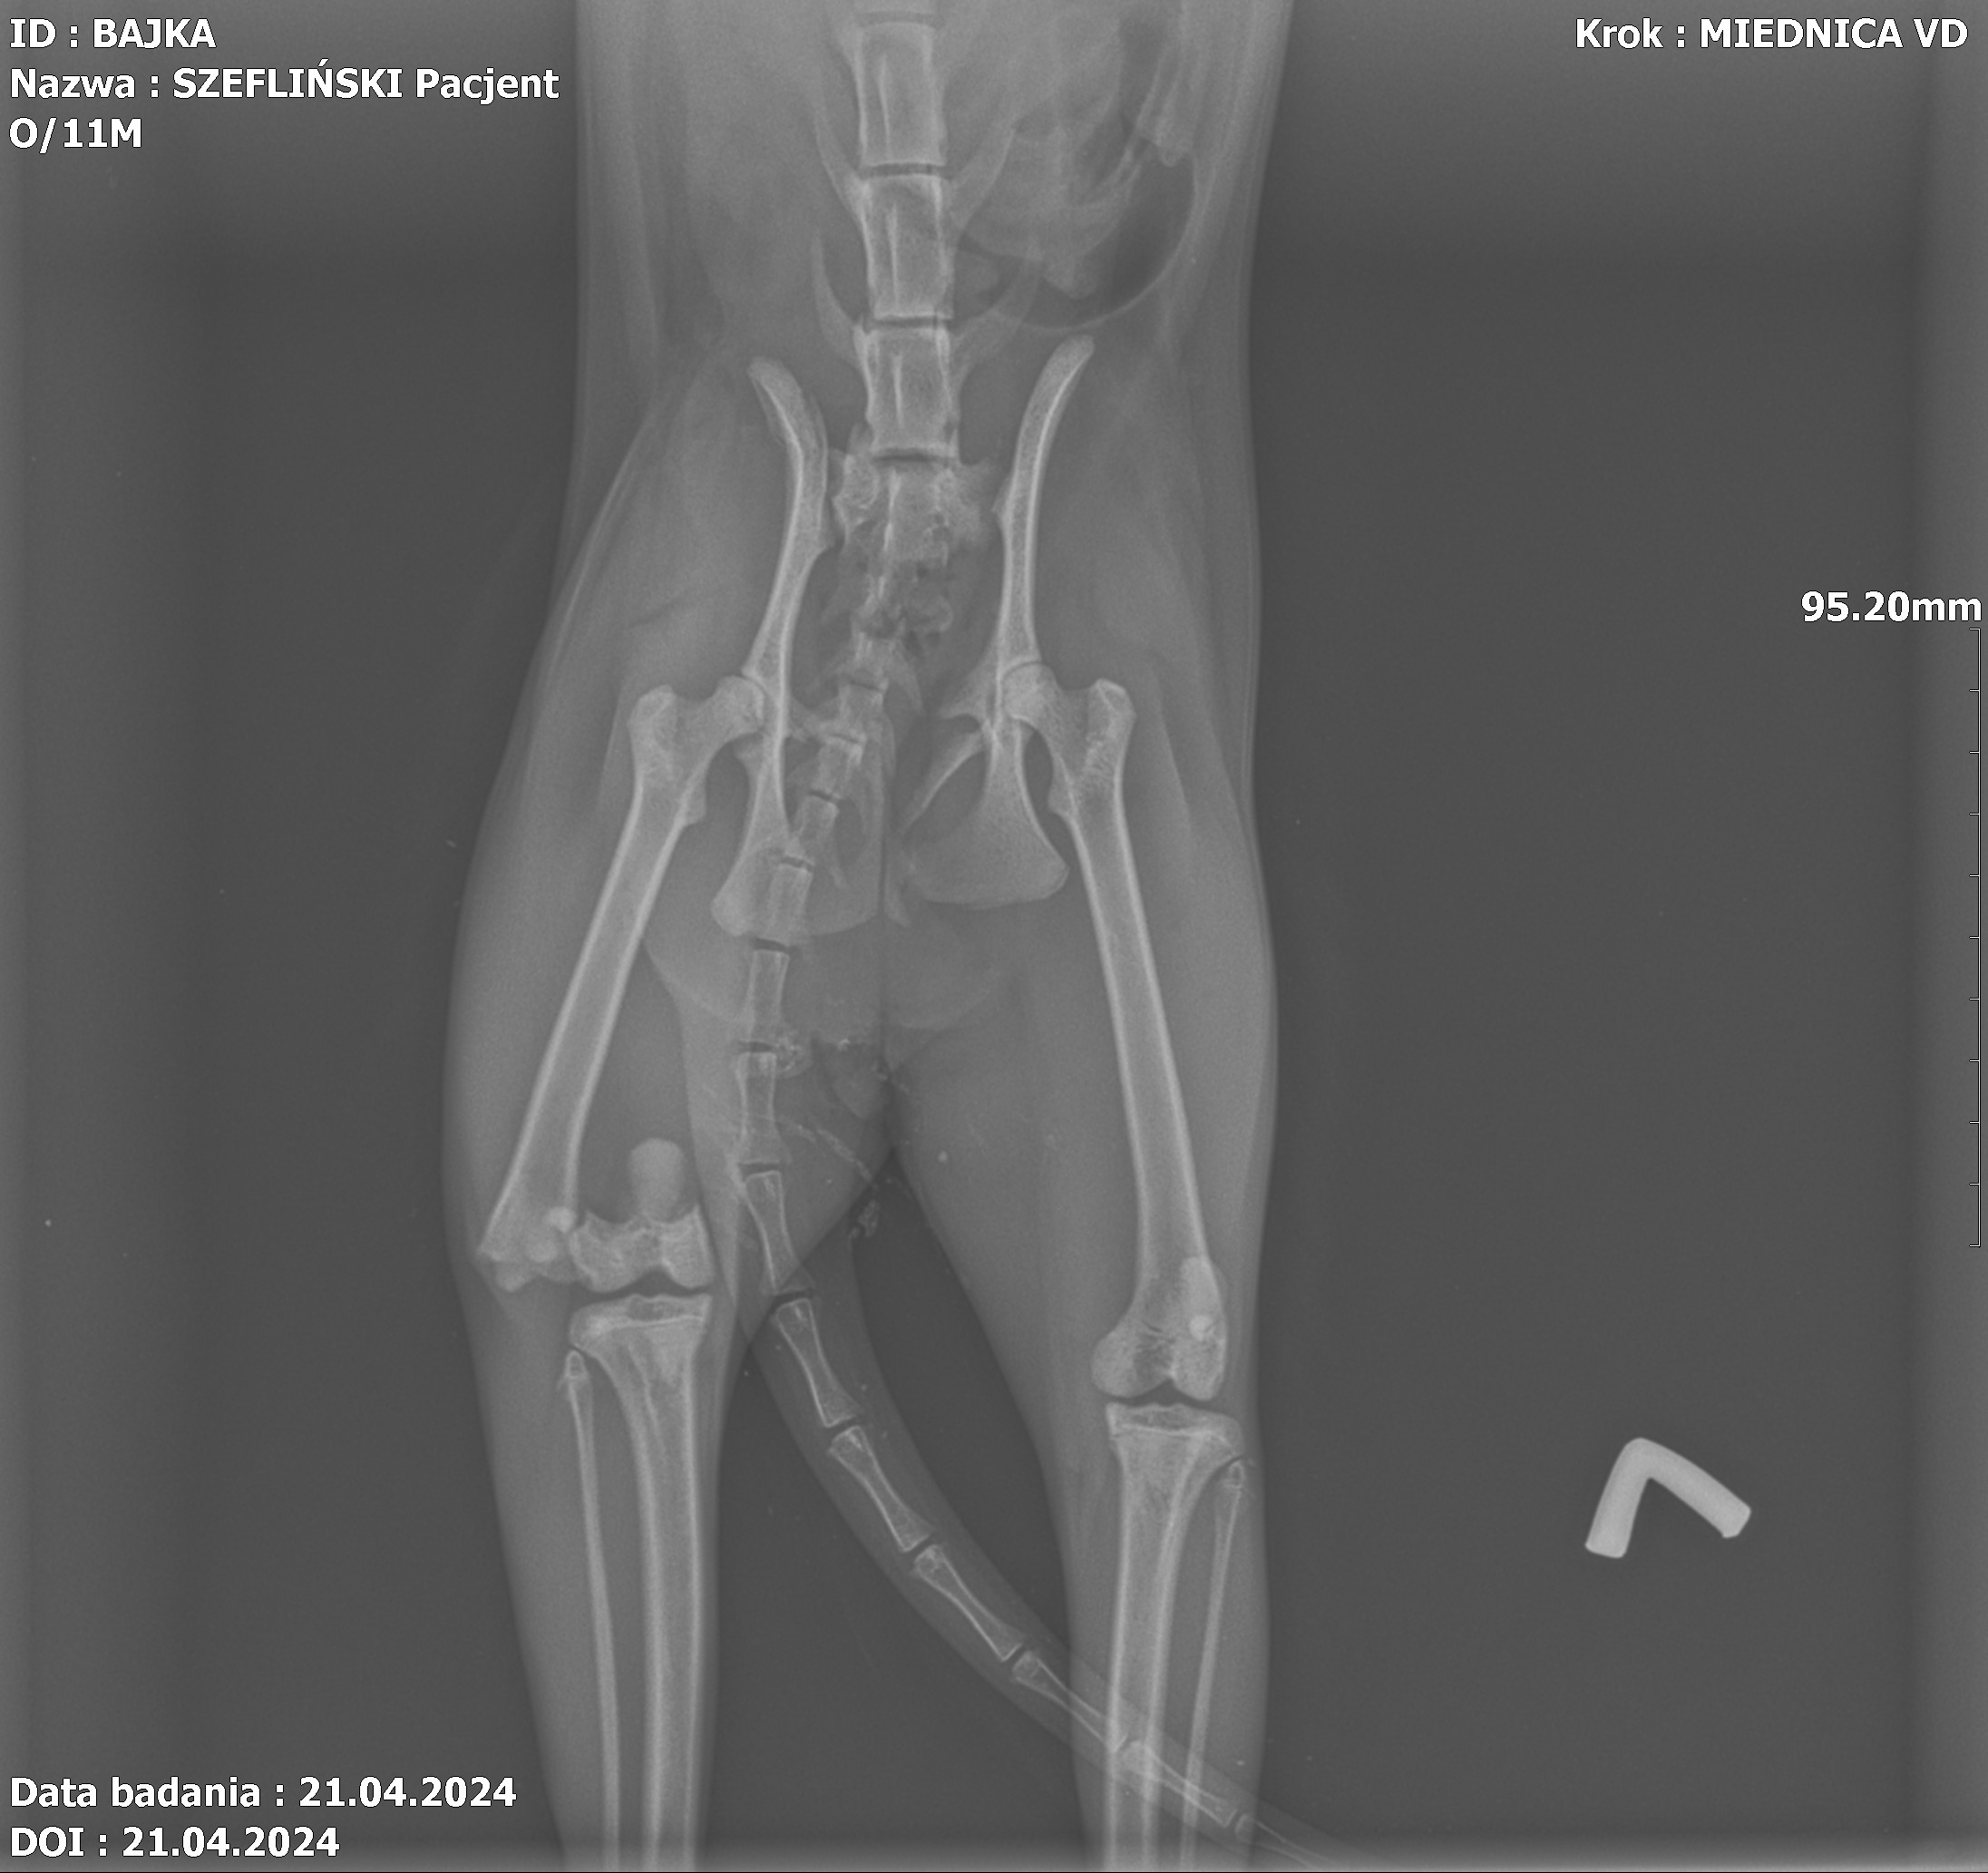

Jest szansa na uratowanie Bajki, ma złamaną prawą tylną łapką i pogruchotaną w kilku miejscach miednicę. Niestety - nasze możliwości finansowe się wyczerpały, życie dość mocno sie ze mną obeszło w ostatnich latach i nie mam generalnie nic. Dziś wydaliśmy wszystkie skromne oszczędności, żeby opłacić leczenie Bajki do tej pory.

Kochani, dzięki Waszym wielkim sercom Bajka dziś pomyślnie przeszła operację - DZIĘKUJEMY ????♥️???? Wielkie brawa dla lekarzy z lecznicy Cztery Łapy w Jeleniej Górze ! Koszt operacji wyniósł 3260 PLN plus każdorazowa wizyta kontrolna 30 PLN plus koszty dodatkowe za miesiąc, tj. wyjęcie śrub, leki, rehabilitacja. Dziś zapłaciłem 3000 PLN, załączam rachunek. Następne załączę przy kolejnych opłatach. Bajka wysyła miaubuźki (. ❛ ᴗ ❛.)